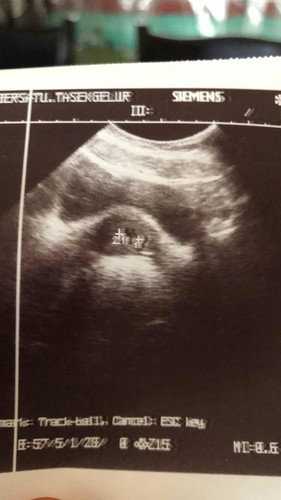

baru 4weeks saya g scan sbb nk cmfm ada ke x.. lps tu doktor cakap rahim dgn kantong bby dah jatuh ?? ada ka ini serius 😭😭 sblm ne saya tak tahu saya prgnt. ada sapa sapa penah alami mcm saya x??